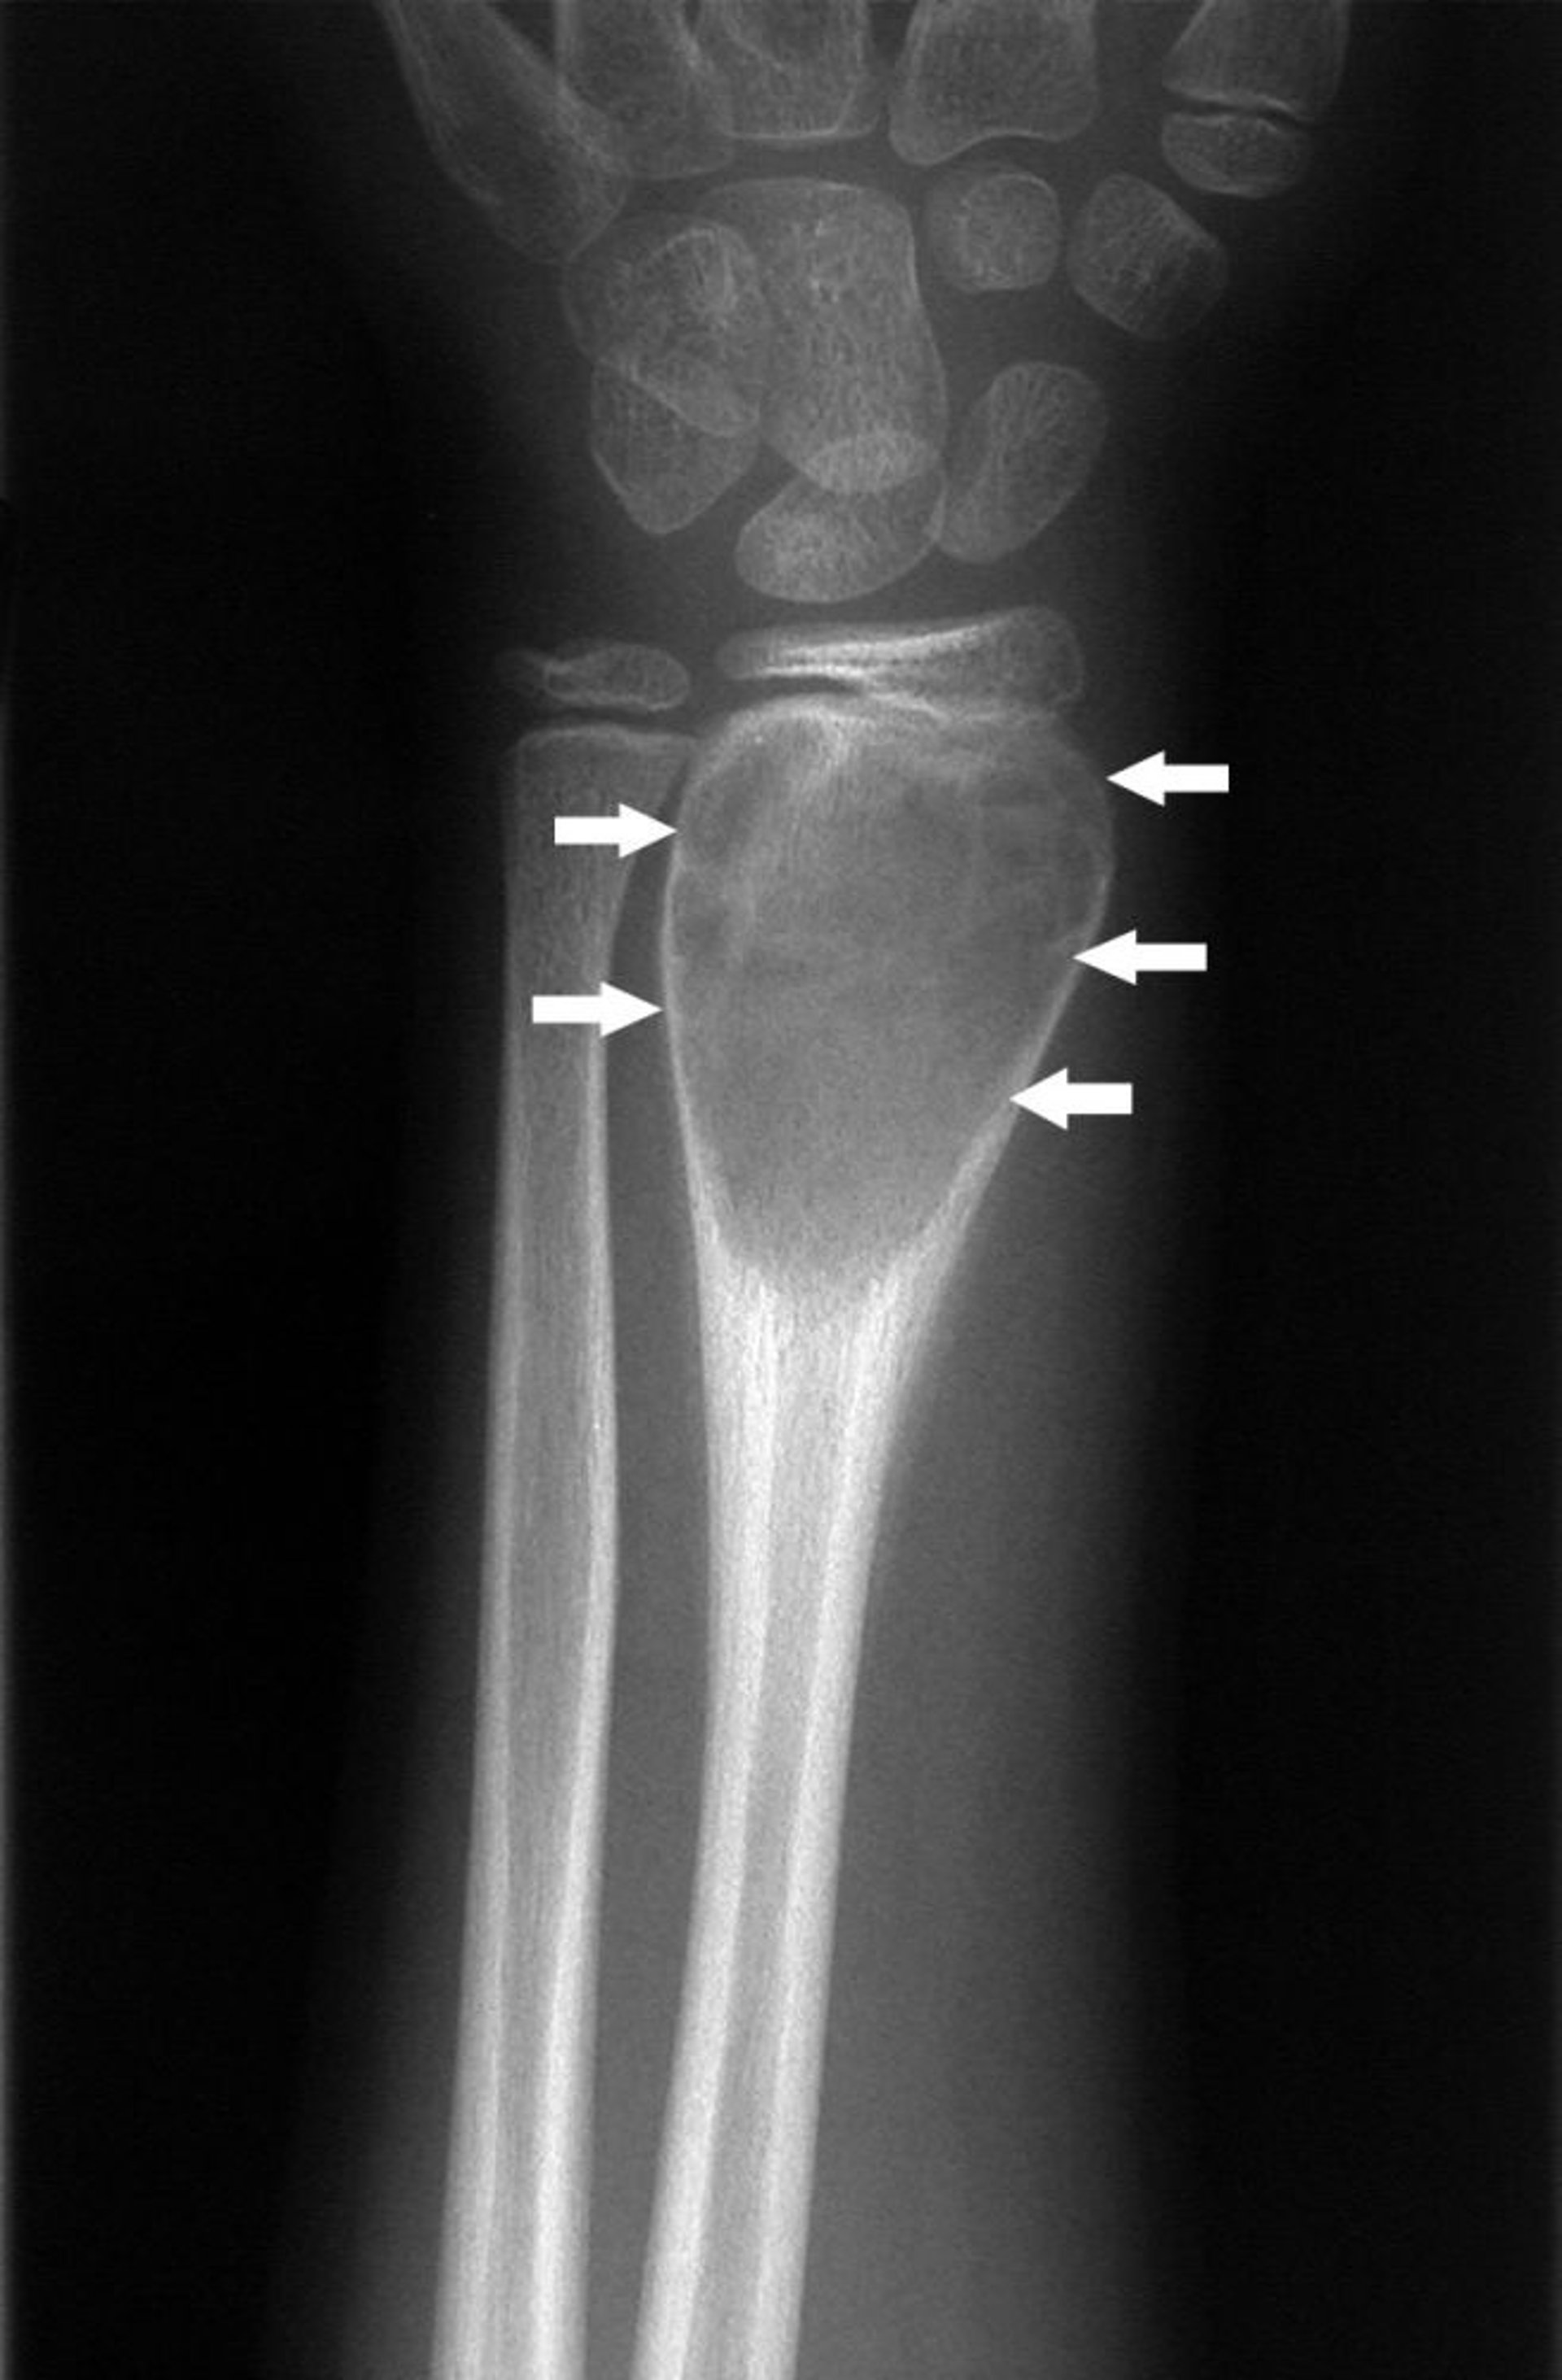

Kyste osseux anévrismal du poignet

Cette radiographie du poignet montre une formation de nouvel os périosté autour de la lésion expansive (flèches), caractéristique d'un kyste osseux anévrismal.

Image courtoisie de Michael J. Joyce, MD, and Hakan Ilaslan, MD.